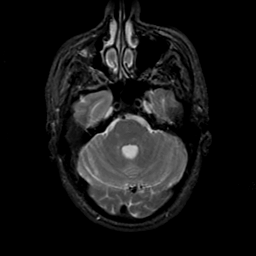

MR Study #19, August 25, 1991 -- Slice #13

[Home][Help][Clinical][Tour 1][Tour 2] Slice 13